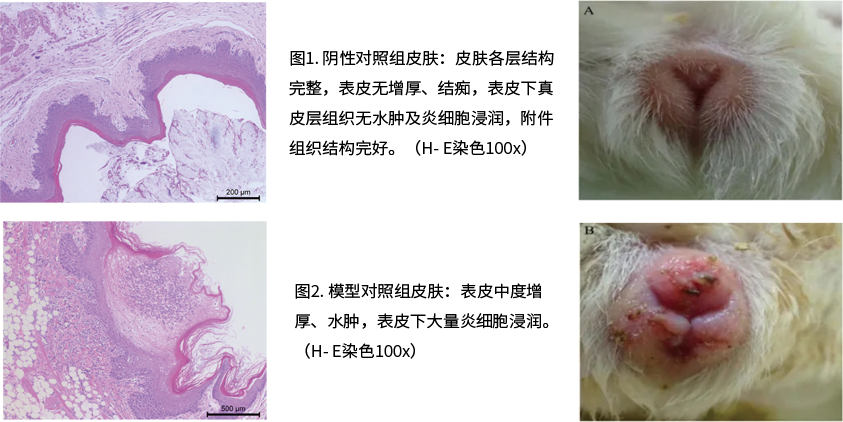

豚鼠皮肤单纯疱疹病毒(HSV-1)模型

豚鼠单纯疱疹性阴道炎(HSV-2)模型